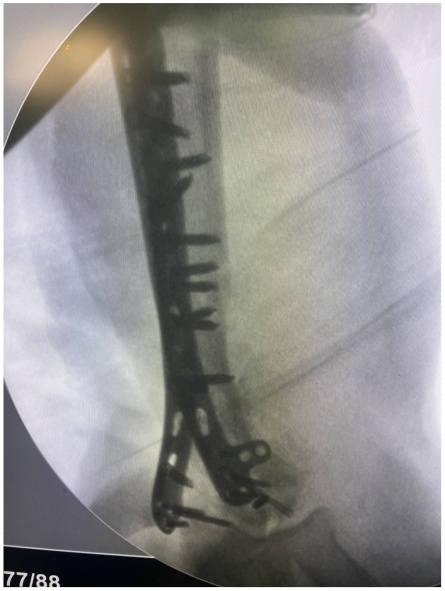

患者徐女士,58岁,因“高处坠落伤致右上臂肿痛、畸形、活动受限2小时”入院。患者于2小时前在家中不慎从3 m高的梯子上不慎掉落摔倒伤及右上臂,即感右上臂剧烈疼痛伴明显活动受限,遂至我院就诊,查体见右上肢三角巾悬吊中,皮肤感觉正常,右上臂中下段及前臂明显肿胀、屈曲畸形,肌张力明显增高,肘关节前侧及内侧皮肤可见张力性水疱,未见明显皮下瘀斑,触痛明显,轴向叩击痛(+),右肩、肘关节活动度因疼痛不能查及,肘后三角关系正常,腕关节及各手指活动度正常,桡动脉搏动可触及,末梢血运良好。急诊行右肱骨X线片检查,提示:右侧肱骨干及肱骨外侧髁可见骨折线影。遂以“右侧肱骨干骨折”收入院。因肱骨干中下1/3段后外侧骨表面有桡神经沟,为防止骨折端不稳损伤刺破神经及肱动脉,故给予右上肢石膏外固定,止痛、消肿等对症治疗,嘱其抬高患肢,抓绕手指。入院后完善右肱骨CT (平扫,三维重建)检查(见图1),提示:右肱骨干、肱骨小头、肱骨滑车、肱骨外侧髁、内侧髁、桡骨头可见骨质多发断裂,断端对位对线欠佳,局部成角,断端分离移位,周围组织增厚,尺骨近段未见异常,右肘关节腔内见片状液体密度影。最终临床诊断为:右侧肱骨干骨折、肱骨滑车骨折、肱骨小头骨折、肱骨内外髁骨折、桡骨头骨折。完善术前相关检查,未见明显异常及相关手术禁忌症,待患肢肿胀情况明显消退后,根据术前影像学资料及患肢的皮肤条件(右肘前侧及内侧皮肤因张力性水疱导致皮肤破溃),最终手术方案选择在插管全麻下行后侧经尺骨鹰嘴截骨入路切开复位双钢板内固定术。

Figure 1. Preoperative CT scan of the elbow joint with plain imaging and 3D reconstruction

1. 术前肘关节CT平扫及三维重建